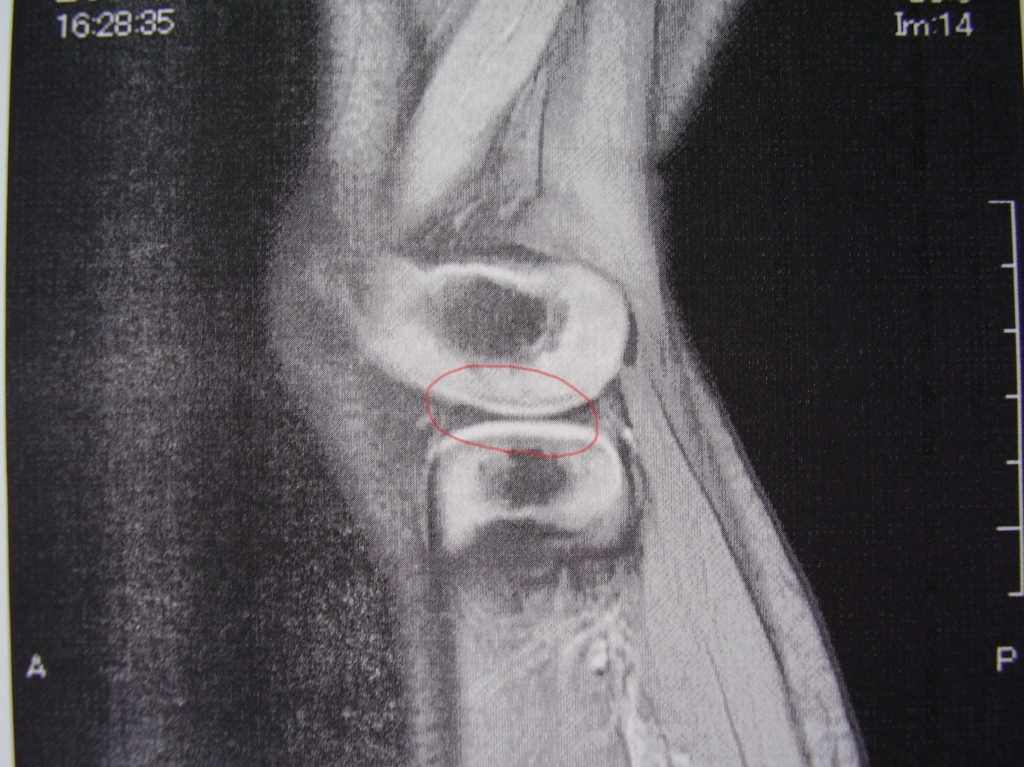

JUGEMテーマ:接骨院・整骨院 先週来院された患者さんが、整形外科を受診され、MRI検査の結果をお持ちいただきました。 外側の半月板が円板状です。 患者さんは、接骨院受診された翌日には、いつ通り元気に飛び回っていたそうです。 お大事に😊